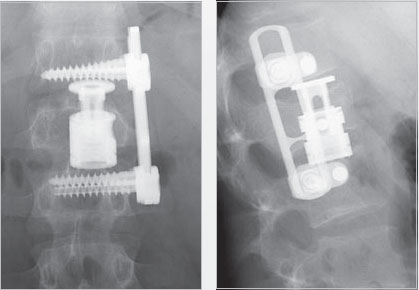

Мужчина, 22 года, саркома Юинга (Ewing's sarcoma). Корпэктомия с замещением тела имплантом Obelisc, фиксация транспедикулярной системой